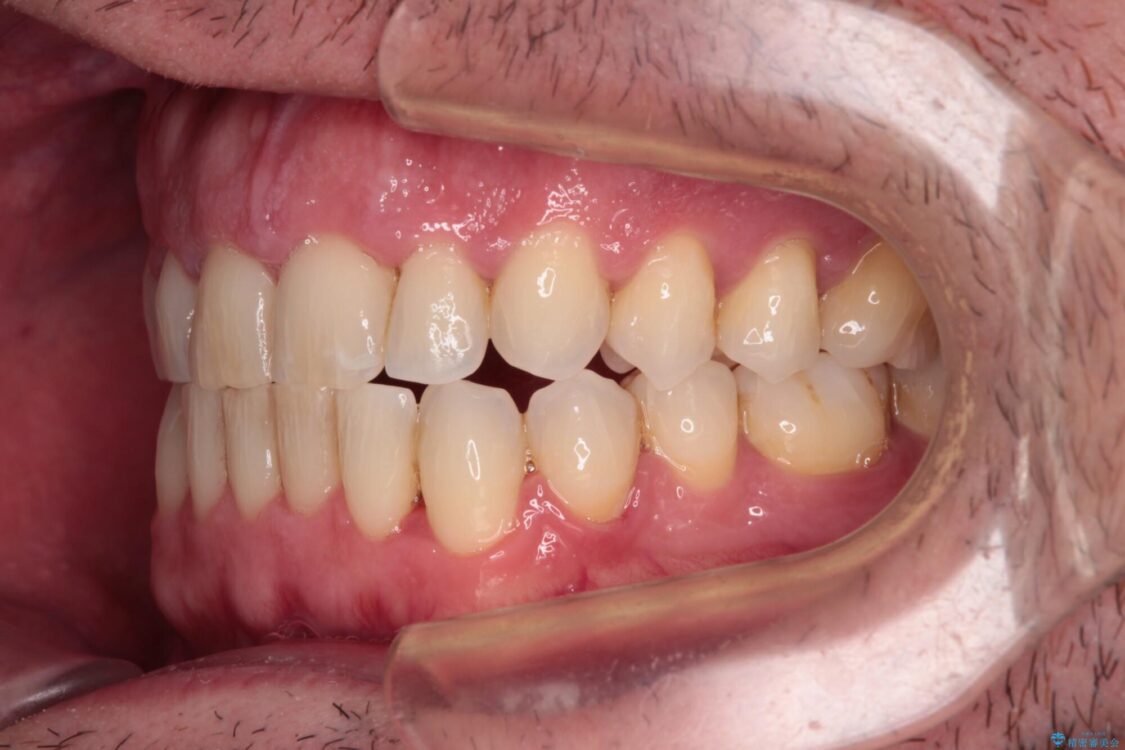

治療後について

舌のトレーニング自体は簡単なものですが、無意識下でも舌が突出しないようにしなければならないため、毎日継続することが最大の難関です。

時間はかかりましたがトレーニングを頑張ってくださり、無事に前歯を接触させることができました。

治療後

• 前歯でものを噛みきりたい 目立たない装置でのワイヤー矯正 治療後画像